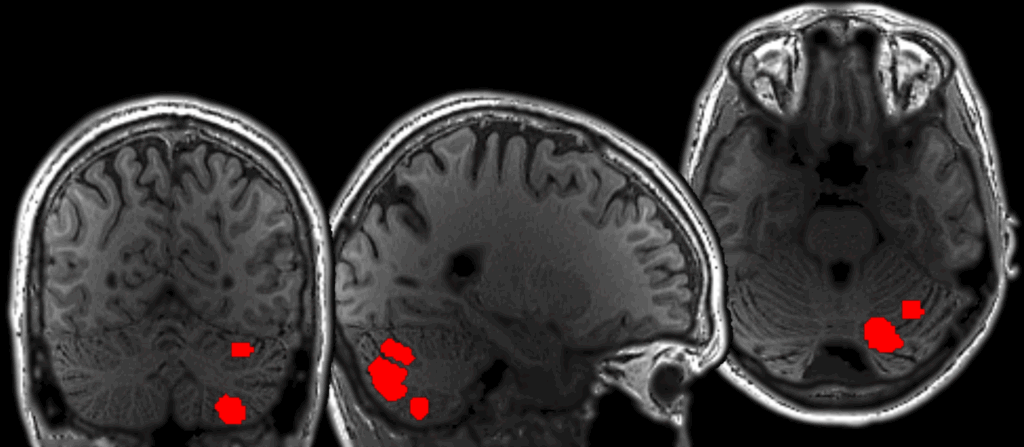

The study, recently published in the journal Neuron, provides evidence that language processing relies on an extended network of brain regions. Specifically, the researchers found three cerebellar regions showing mixed responses to language and to non-linguistic tasks, and one region that is selectively tuned to language in much the same way as established cortical language areas.

In this study, researchers used functional magnetic resonance imaging (fMRI) to examine brain activity in human participants performing 26 tasks, including reading, listening, speaking, solving math problems, completing memory exercises, and processing visual stimuli. This allowed the team to compare how different cerebellar regions responded to linguistic and non-linguistic demands.

Casto and his team found four regions in the cerebellum that respond to language, but, importantly, the regions did not all respond in the same way. One region responded exclusively to language. The remaining three cerebellar regions showed a different response profile. In addition to language, they were active during motor tasks, demanding non-linguistic tasks, and/or the processing of meaningful visual stimuli.

A key reason these cerebellar patterns have been difficult to detect in past studies lies in how most fMRI studies are conducted. Typically, researchers average brain activity across many participants to identify regions that respond reliably to a given task. While powerful, this approach can obscure fine-grained organization, especially in a structure like the cerebellum, where regions performing distinct functions are densely packed and vary substantially from one individual to the next.

Instead, Casto’s team localized language-responsive regions within each participant’s cerebellum before examining how those individualized regions responded across tasks.

This individual-level analysis had the power to disentangle overlapping signals that would otherwise be smeared together, producing a much sharper understanding of cerebellar involvement in language.